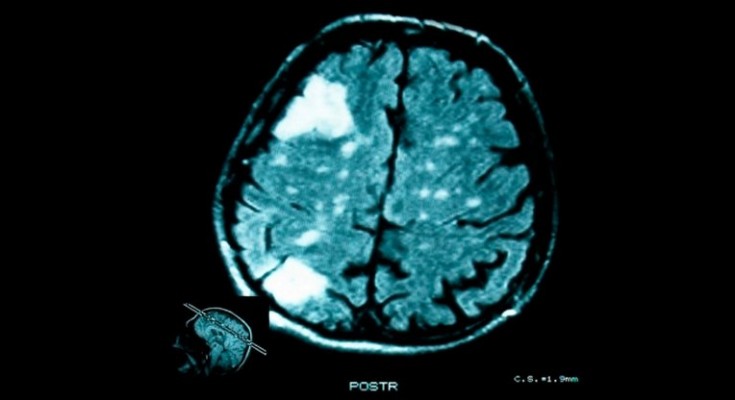

Para el estudio publicado en la revista ‘Nature Genetics’ se analizaron 904 tumores de 14 tipos de cáncer y descubrieron que la evolución de 323 tumores, incluidos de estómago, intestino y algunos cánceres de pulmón, podían predecirse mediante la aplicación de este modelo, destaca RT.